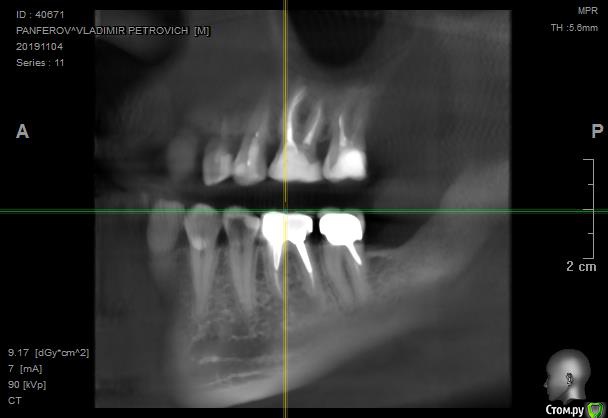

в 2011-м году 6-й снизу справа зуб был депульпирован, спустя несколько лет установлена коронка с ВКВ

Перед заменой коронки на соседнем зубе сделали контрольный снимок, обнаружили кисту.

Лечащий врач считает невозможным извлечь ВКВ. С учетом того, что зуб не беспокоит предложила сделать контрольный снимок через год и там принимать решение об удалении в зависимости от роста кисты.

Если мы рассуждаем о жизнеспособности данного (6-го) зуба, то его прогноз ухудшается наличием процесса между корнями в первую очередь, а кистой во вторую.

Уверен на 90%, что извлекая вкладку из данного зуба, ему можно подписать приговор на удаление.